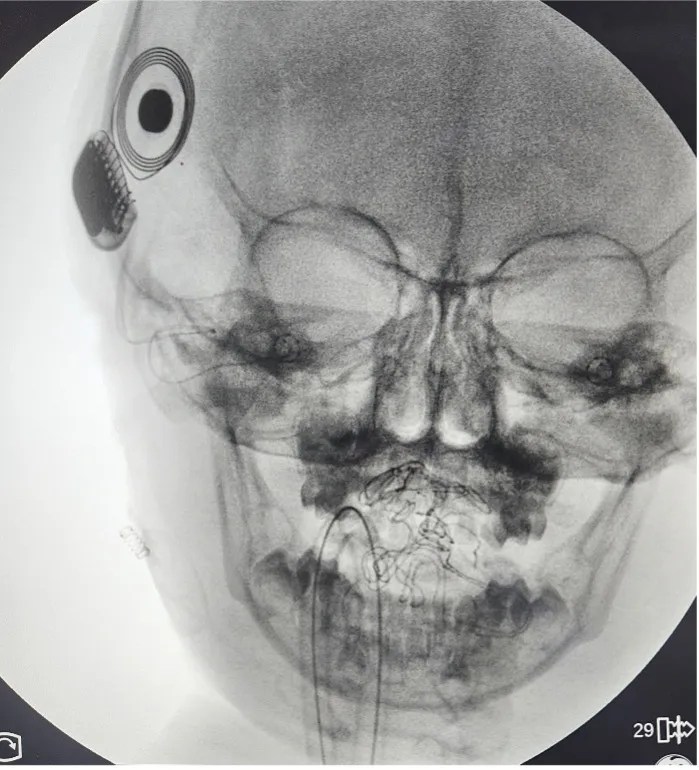

A 3-year-old boy with bilateral congenital profound sensorineural hearing loss was given a chance to hear his parents’ voices, enjoy the sounds around him, and developmentally keep up with his normal-hearing peers.

Our Otologist, Dr. Giselle Gotamco-Lo, performed the first Cochlear Implant Surgery at Chinese General Hospital and Medical Center last January 9, 2026.

Patients with congenital hearing loss are identified through Newborn Hearing Screening. A “refer” result prompts further testing through Auditory Brainstem Response for diagnosis. Once diagnosed, patients undergo hearing rehabilitation. If no benefit is seen from hearing aids, a patient may be advised to undergo cochlear implant surgery.